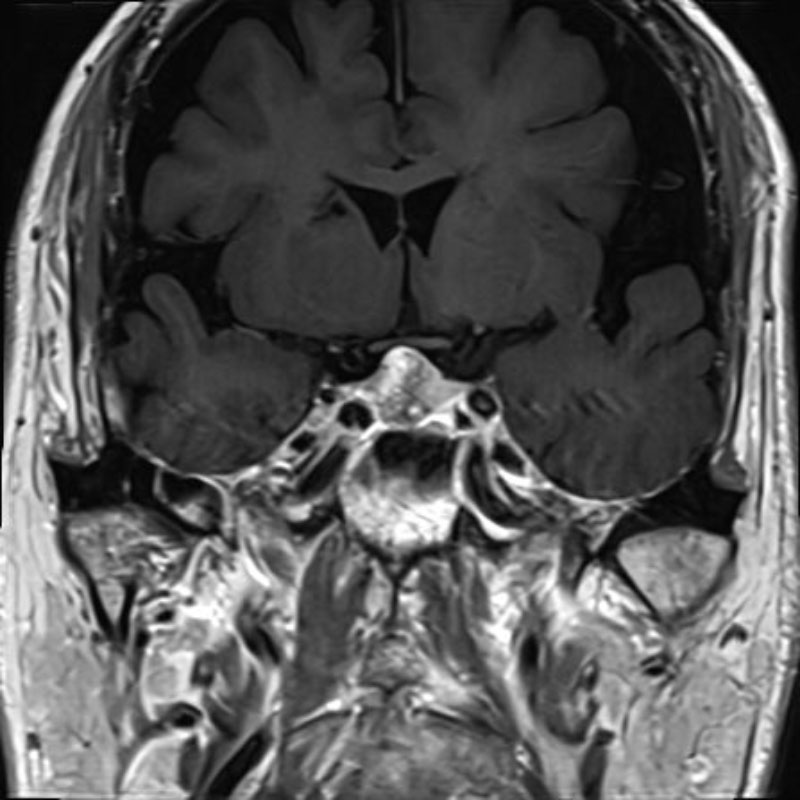

下垂体腫瘍

頭蓋内腫瘍摘出術

No.’25_74 手術前1

No.’25_74 手術前2